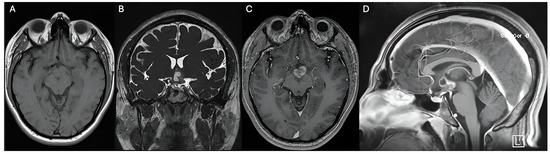

Figure 1. Preoperative MRI shows a hypothalamic lesion that is isointense on T1 (A), hyperintense on T2 (B), partially enhances contrast (C), and has a small cystic component superiorly (D). No evidence of calcifications. The hypothalamic lesion has an approximate volume of 8.03 cm3.

The MRI was subsequently conducted using a navigation protocol, which revealed a well-circumscribed lesion in the hypothalamic region that was clinically and anatomically consistent with a low-grade astrocytoma. The optic chiasm, pituitary stalk, and adjacent neurovascular structures were all in close proximity to the tumor, which presented substantial risks if conventional surgical intervention were pursued.

Due to the clinical and radiological diagnosis of a pilocytic astrocytoma, classified as a low-grade astrocytoma (WHO Grade I), the primary treatment selected was gamma knife radiosurgery (GKRS). This decision followed extensive multidisciplinary discussions and thorough consultation with the patient’s surrogate (Figure 1). The high-risk anatomical location of the hypothalamic lesion, where traditional open surgical resection posed significant morbidity risks—such as damage to critical neurovascular structures—was a key factor. Given the lesion’s proximity to the optic pathways, pituitary gland, and other vital neuroendocrine structures, GKRS was deemed the most appropriate intervention due to its precision and minimally invasive approach, offering targeted therapy with a reduced risk of neurological deficits (Table 1).

4.1. Hypothalamic Gliomas—Radiologic Characteristics